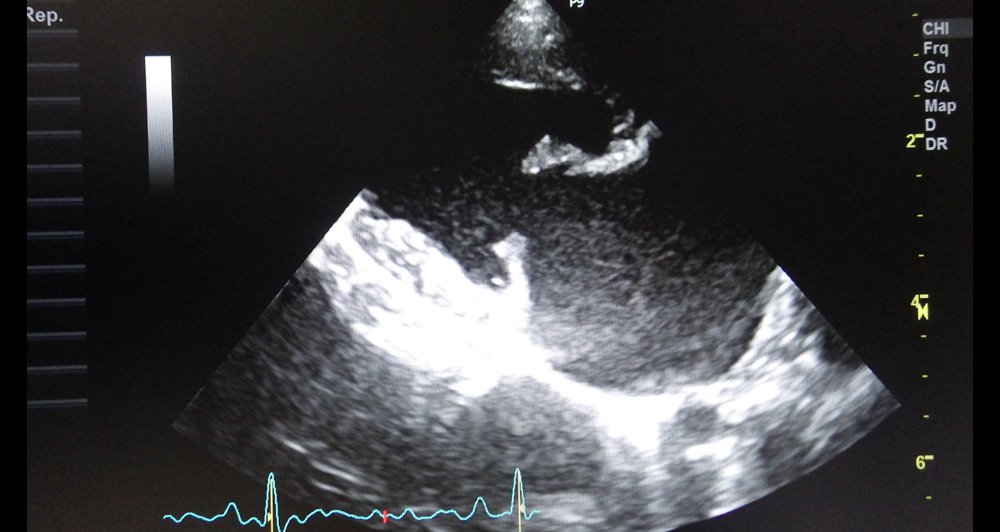

犬の僧帽弁閉鎖不全症

Mitral valve insufficiency

心臓の中では血液は一方通行で流れています。そのために心臓の各部屋の間には弁がついており、その一つが僧帽弁です。